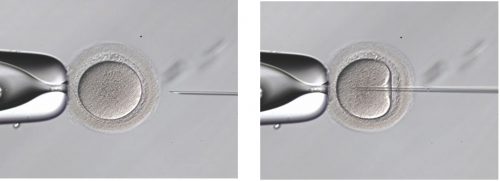

3.受精(卵管内での受精)